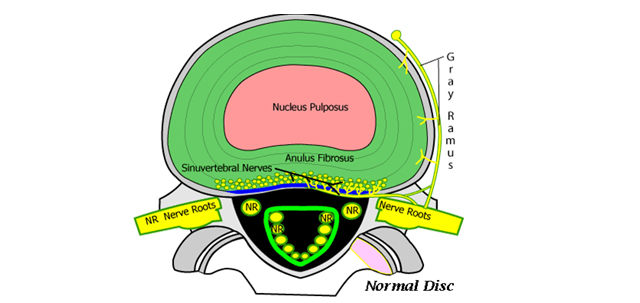

Çfarë ndodhë tek ndryshimi degjenerativ i diskut?

Së pari, nga bërthama fillon të humbet uji e pastaj disku fillon dhe bëhet më i fortë. Kështu, e humbë aftësinë e absorbimit të ngarkesës (forcës), pastaj mbështjellësi fibrozë rreth diskut e humb aftësinë e elasticitetit, anulusi dobësohet dhe, si pasojë e kësaj, vjen deri te kërcitja e tij dhe rrjedhja e përmbajtjes xhelatinoze nga bërthama e diskut jashtë. Kështu, së pari fillon si diskus herni, e me pastaj vjen duke përfunduar në pasojat e diskut të degjeneruar.

Pasi një disk të humbë përafërsisht 80% të lëngut (ujit) të tij, atëherë ai quhet i degjeneruar. E tërë kjo mund të shkaktojë radikulpati, stenozë apo ngushtim të kanalit spinal dhe artrozë të hapësirës mes unazave, e cila mund të jetë e përcjellur edhe me humbje të masës kockore minerale dhe dhënie të deformimeve të shtyllës kurrizore si pasojë e këtyre ndryshimeve. E gjithë kjo, mund të shpie edhe në dhembje të shtyllës kurrizore.